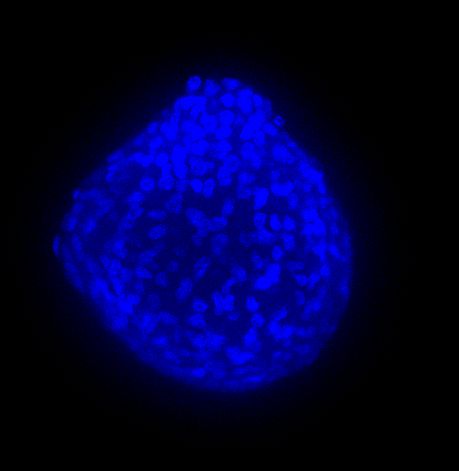

We performed acquisitions with CrestOptics X-Light V3 spinning disk confocal coupled with Prime BSI Camera (Photometrics, 6.5 um pixel size). We compared acquisitions performed with 20x air objective (CFI Plan Apo Lambda, Nikon, 0.7 NA and 1mm WD) and 25x silicone oil objective (CFI Plan Apo Lambda S, Nikon, 1.05 NA and 0.55 mm WD). In Figure A, we show maximum intensity projection (MIP) images obtained from Z stack of 150 um total; in particular, the same spheroid was acquired with 20x air objective and with 25x silicone oil objective. Figure B shows a zoom of the same region of the 3D spheroid acquired with both lenses.

The comparison between the images acquired with the 20x air objective and those with the 25x silicone oil objective (Figure A, B and C) highlights the importance of the lens choice based on the biological application. The transition from 20x to 25x leads to a gain in resolution (based on the greater NA of the 25x compared to the 20x NA), which certainly affects the image quality, and also leads to a reduction in the light refraction. As a matter of fact, immersion oils greatly improve the microscope’s resolving power by replacing the air gap between the lens and the coverslip with a higher refractive index medium, thus allowing to reduce the refraction of light.

In 3D imaging, matching the refractive index of the sample and its immersion medium is crucial for deep tissue observation. Silicone immersion oil is perfect for imaging through thick biological samples; it closely matches the refractive index of cells and of the mounting medium, decreasing spherical aberration and resulting in brighter and higher resolution images compared to those acquired with a common 20x air objective.

Figure A 3D tumor spheroids: MIP from Z stack of a cancer spheroid acquired with 20x air objective (TOP) and 25x silicone oil objective (BOTTOM). Living cells are marked with Calcein (green) and dead cells with PI (red). Nuclei are stained with Hoechst (blue). Scale bar: 100 um. These images were acquired with CrestOptics X-Light V3 spinning disk.